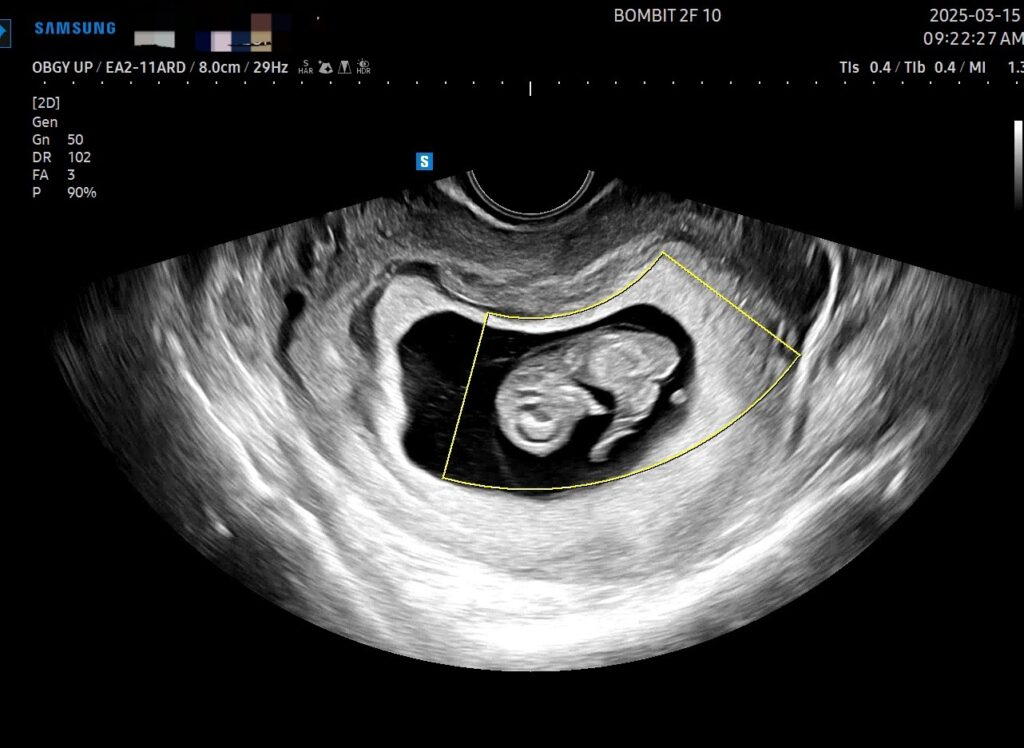

3월 15일에는 봄빛병원에 방문해서 세번째 심장소리를 들었다.

아기가 다리도 아주 약간 움직였는데, 조그만 게 다리를 움직이는 것이 대견했다.

이 날의 병원 방문에서, 아기집 주변에 피고임이 있다고 알려주었고, 이에 호르몬 약도 함께 처방해 줬다.